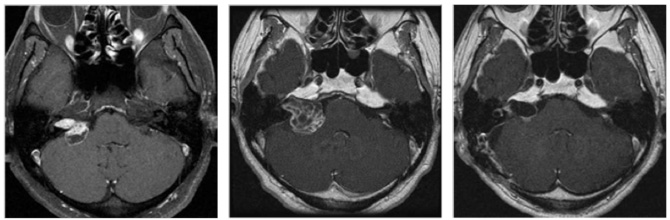

図3はガンマナイフ後、残念ながら増大してしまった50代男性の腫瘍です。聴覚はすでに失われておりましたので、注意深く顔面神経を保護しつつ手術を行い、95%摘出しました。術後問題なく社会復帰されています。

図3:50代男性 ガンマナイフ後3年半で拡大

(左図)ガンマナイフ時(中図)3年半後(右図)手術後 術後4年経過するも再増大なし